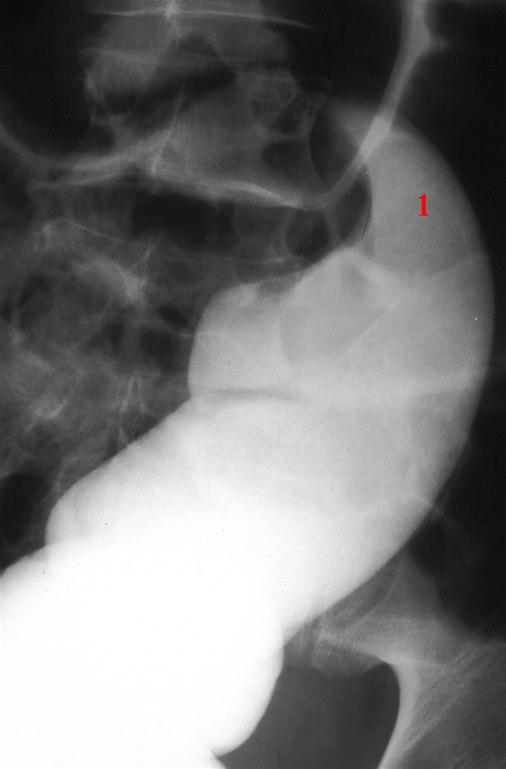

Ved mistanke om tarmslyng blir man lagt inn på sykehus. Her vil det bli gjort grundige undersøkelser både i form av legeundersøkelse, blodprøver, CT-undersøkelse og eventuelt vanlige røntgenbilder. Røntgenlegen vil kunne påvise om det er stans i tarmpassasjen.

Koloskopi kan være nyttig både diagnostisk og terapeutisk - det er noen ganger muilg å rotere tarmen tilbake - se mer nedenfor. Undersøkelsen kan også gjøres for å bedømme om tarmen er varig skadet. Prosedyren må umiddelbart avbrytes dersom det ses tegn til koldbrann i tarmen (gangren).